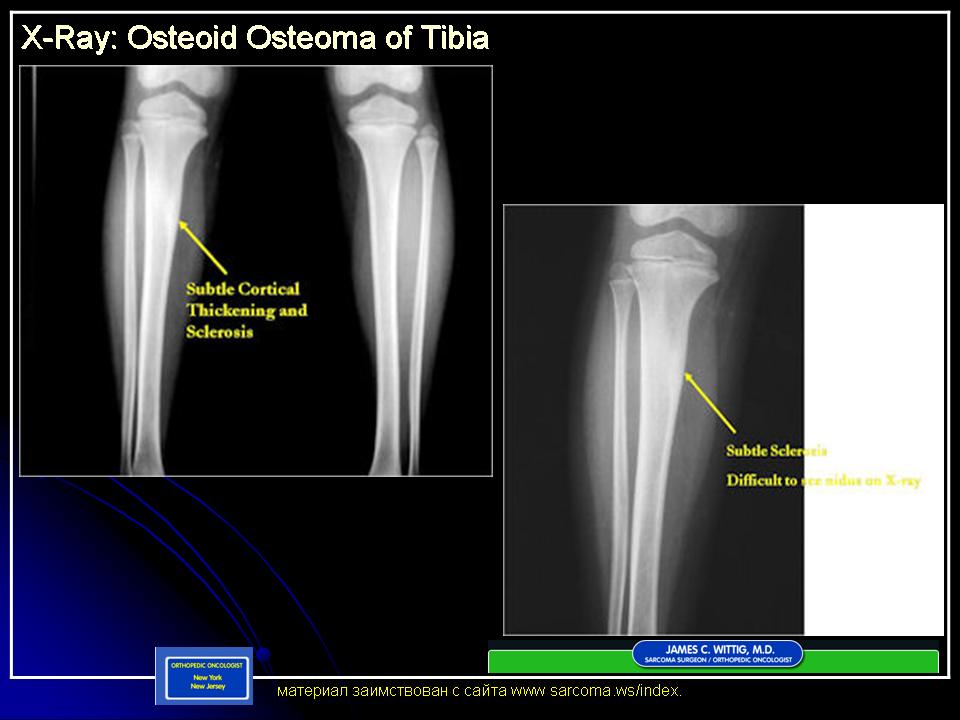

Первичные костные опухоли.

Остеома

Регулярно проходите медицинские осмотры и делайте рентген для контроля роста остеомы.